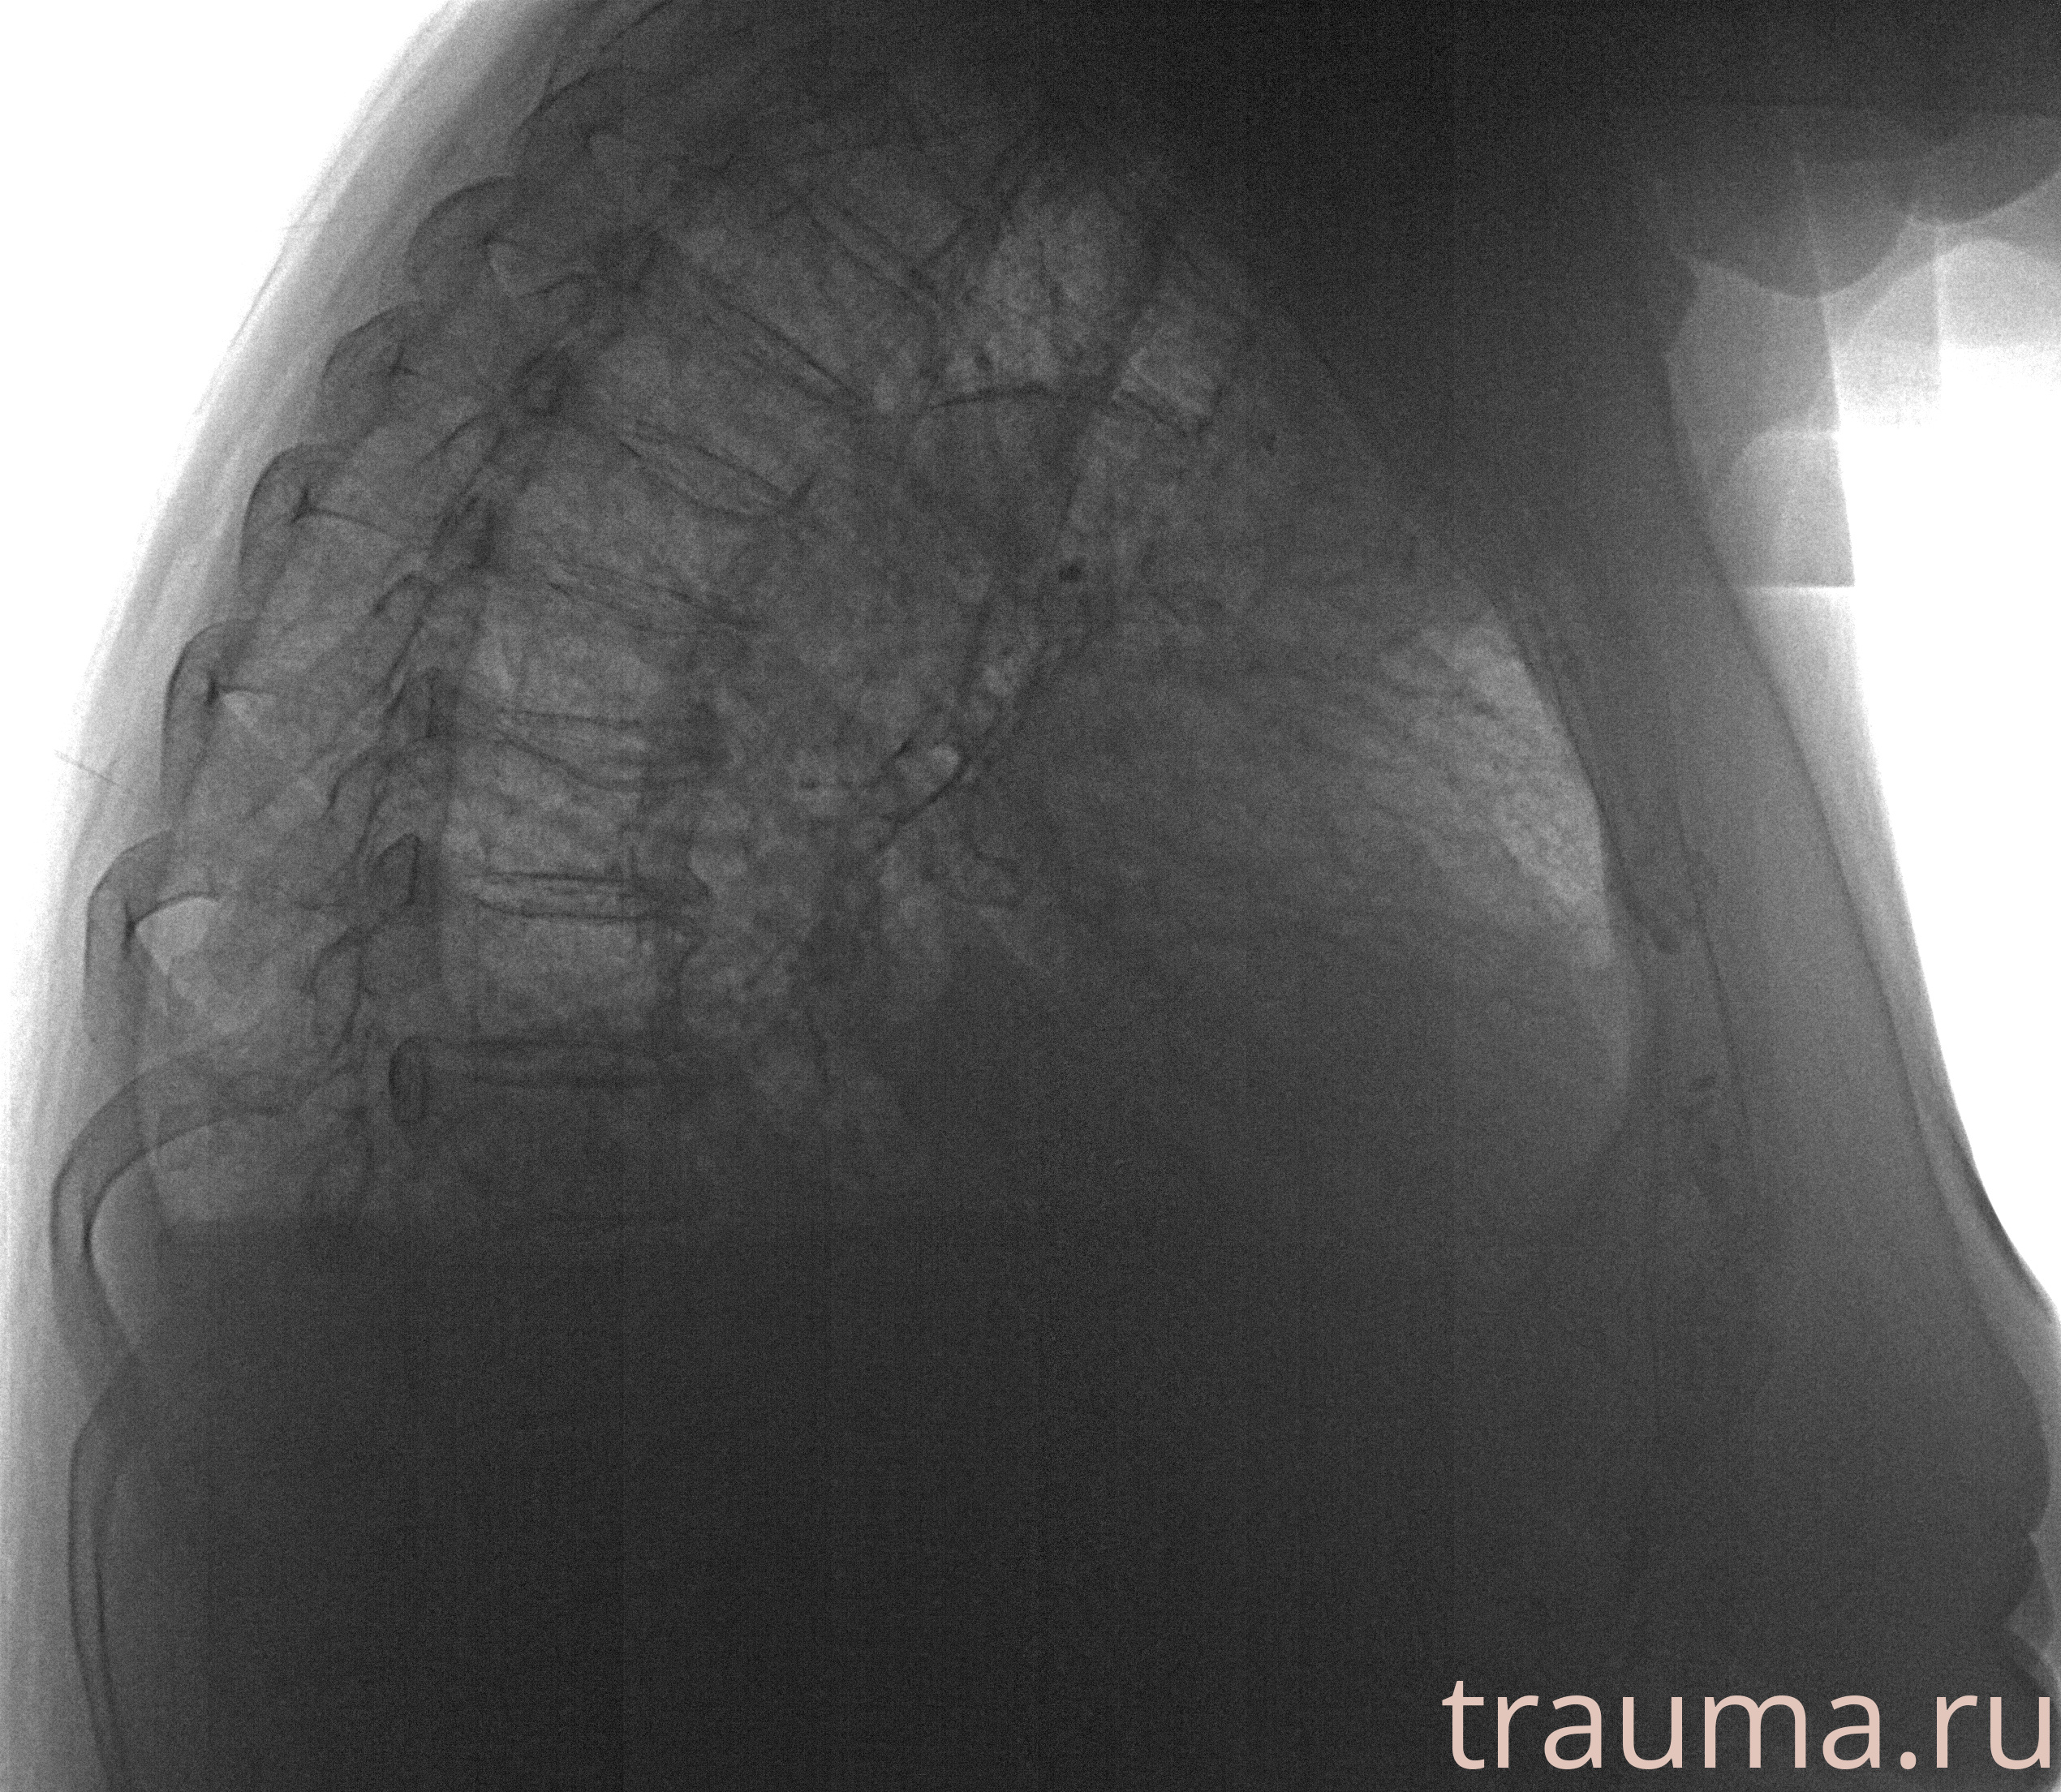

Рентгенограммы

Рентген на дому: по вашему адресу приезжает врач-рентгенолог, травматолог-ортопед с мобильным рентгеновским аппаратом, проводит диагностику травмы или заболевания, делает необходимые рентгенограммы, дает рекомендации по дальнейшему лечению. Получить качественные снимки в домашних условиях возможно благодаря уникальной методике, разработанной МосРентген Центром для института  Склифосовского